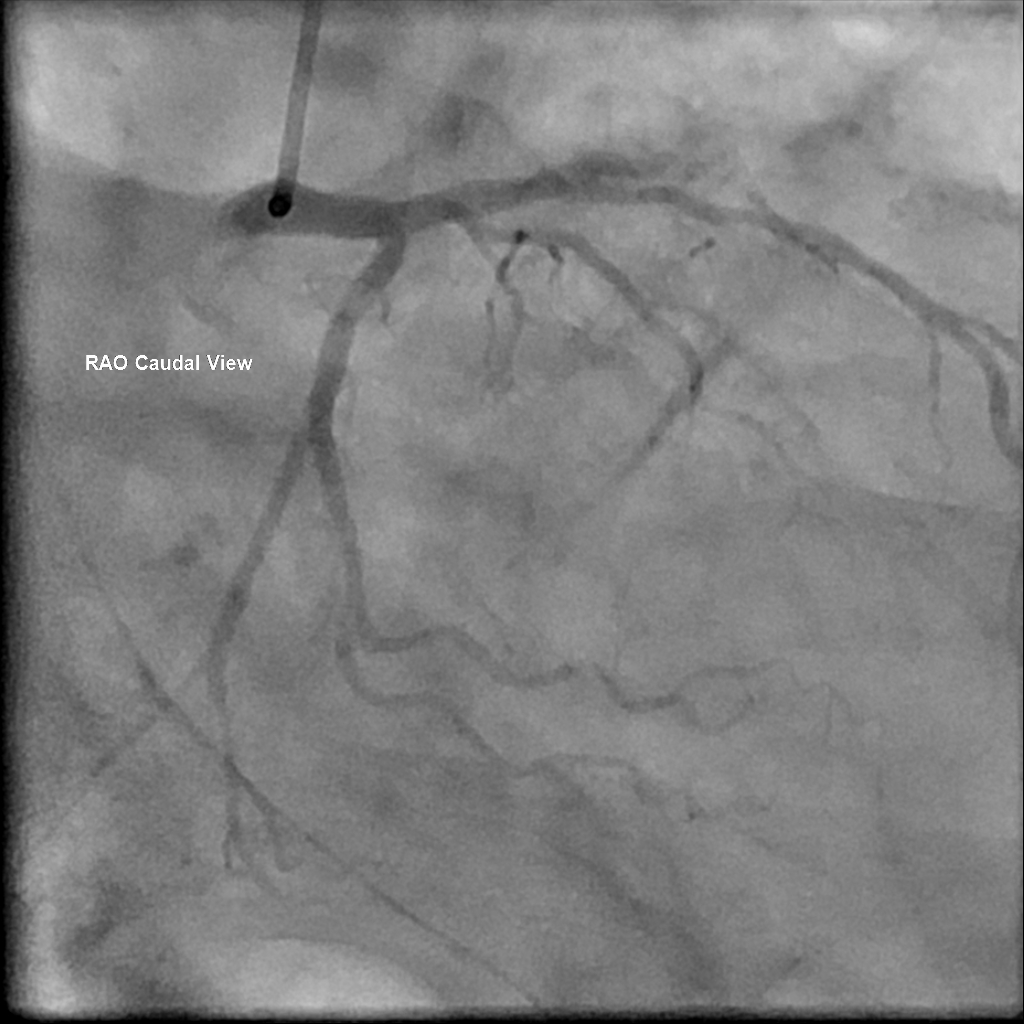

CAG: LAD-M total occlusion